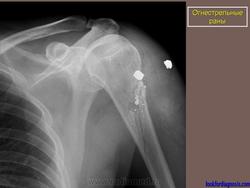

Огнестрел и военные действия.

1.ogn_.1.rd_.slayd59.jpg3.ogn_.2.rd_.slayd69.jpg4.ogn_.16.i.slayd15.jpg